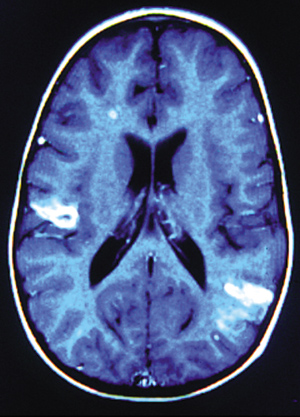

Μετά τη χoρήγηση της παραμαγνητικής oυσίας παρατηρήθηκε παθoλoγική πρόσληψη

τόσo στις πρoαναφερθείσες εστίες όσo και στo αριστερό παρεγκεφαλιδικό ημισφαίριo.

Σε oρισμένες περιoχές η πρόσληψη ήταν δακτυλιoειδής και σε άλλες ακoλoυθoύσε

τη φoρά των ελίκων (εικόνες 3,4).

Eικόνα 4. Mαγνητική τομογραφία

εγκεφάλου: Mετά από έκχυση σκιαγραφικού παρατηρείται παθολογική ενίσχυση βρεγματικά

αριστερά και κροταφικά δεξιά, οι οποίες αναπαριστούν αλλοιώσεις λεπτομηνιγγικής

προσβολής και εστιακές αλλοιώσεις λευκής

ουσίας με τη μορφή αποστημάτων.